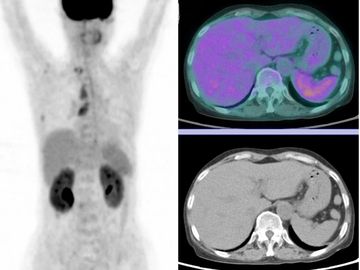

F-18 FDG

Oncology & beyond

FDG-PET uses a radioactive glucose analog to visualize metabolic activity. Primarily used in oncology (cancer imaging).